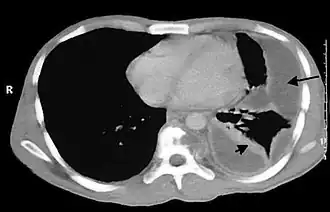

O diagnóstico é sugerido pela anamnese e exame físico, e complementado pela radiologia, exames laboratoriais e toracocentese.

A radiologia é uma ferramenta essencial, e deve ser realizada nas incidências póstero-anterior e perfil. A radiologia permite ainda avaliar de modo grosseiro o tempo de evolução do empiema.